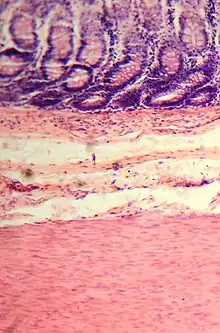

Colonic crypts

The wall of the large intestine is lined with simple columnar epithelium with invaginations. The invaginations are called the intestinal glands or colonic crypts.

Micrograph of normal large instestinal crypts.

Anatomy of normal large intestinal crypts

The colon crypts are shaped like microscopic thick walled test tubes with a central hole down the length of the tube (the crypt lumen). Four tissue sections are shown here, two cut across the long axes of the crypts and two cut parallel to the long axes. In these images the cells have been stained by immunohistochemistry to show a brown-orange color if the cells produce a mitochondrial protein called cytochrome c oxidase subunit I (CCOI). The nuclei of the cells (located at the outer edges of the cells lining the walls of the crypts) are stained blue-gray with haematoxylin. As seen in panels C and D, crypts are about 75 to about 110 cells long. Baker et al.[32] found that the average crypt circumference is 23 cells. Thus, by the images shown here, there are an average of about 1,725 to 2,530 cells per colonic crypt. Nooteboom et al.[33] measuring the number of cells in a small number of crypts reported a range of 1,500 to 4,900 cells per colonic crypt. Cells are produced at the crypt base and migrate upward along the crypt axis before being shed into the colonic lumen days later.[32] There are 5 to 6 stem cells at the bases of the crypts.[32]

As estimated from the image in panel A, there are about 100 colonic crypts per square millimeter of the colonic epithelium.[34] Since the average length of the human colon is 160.5 cm[11] and the average inner circumference of the colon is 6.2 cm,[34] the inner surface epithelial area of the human colon has an average area of about 995 cm2, which includes 9,950,000 (close to 10 million) crypts.

In the four tissue sections shown here, many of the intestinal glands have cells with a mitochondrial DNA mutation in the CCOI gene and appear mostly white, with their main color being the blue-gray staining of the nuclei. As seen in panel B, a portion of the stem cells of three crypts appear to have a mutation in CCOI, so that 40% to 50% of the cells arising from those stem cells form a white segment in the cross cut area.

Overall, the percent of crypts deficient for CCOI is less than 1% before age 40, but then increases linearly with age.[31] Colonic crypts deficient for CCOI in women reaches, on average, 18% in women and 23% in men by 80–84 years of age.[31]

Crypts of the colon can reproduce by fission, as seen in panel C, where a crypt is fissioning to form two crypts, and in panel B where at least one crypt appears to be fissioning. Most crypts deficient in CCOI are in clusters of crypts (clones of crypts) with two or more CCOI-deficient crypts adjacent to each other (see panel D).[31]